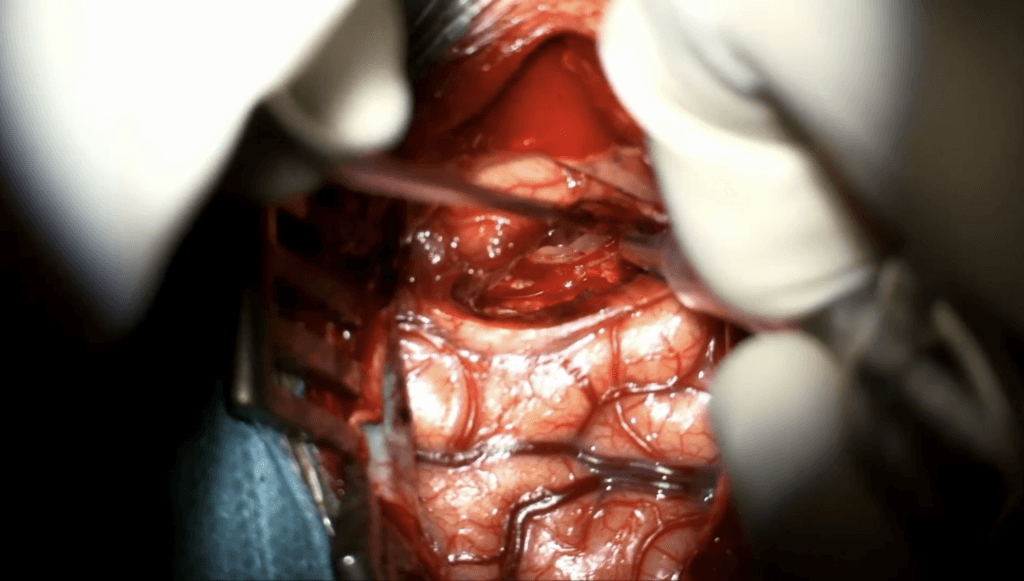

Callosotomía

El Dr. José Manuel Garbizu realiza una callosotomía en un paciente con craneotomía frontal derecha.